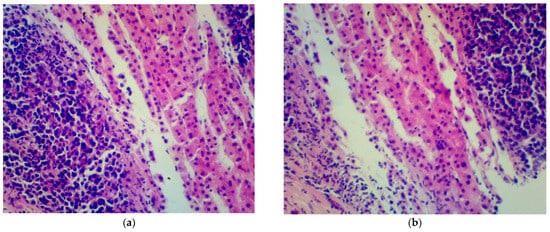

A percutaneous liver biopsy was performed (Figure 1). The histopathological examination described a hepatic tissue with infiltration of plasma cell myeloma. IHC: CD38+, CD138+, chromogranin−, synaptophysin−, and Ki67+ in approximately 80% of cells. The results of the biopsy confirmed that the lesion, which seemed to be an independent tumor, was in fact the outcome of the underlying disease.

Figure 1. Histopathological examination of hepatic tissue (hematoxylin-eosin-stained histological images). Small, dark cells of plasma cell myeloma can be seen (a,b).